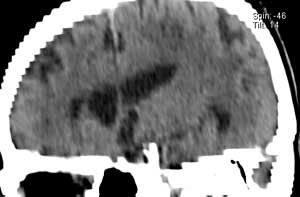

На рис.8 представлены изображения снятые при неудачном (слева) и правильном

(справа) выборе параметров съемки.

Рисунок 8

-Изображения, полученные при разных значениях параметра съемки.